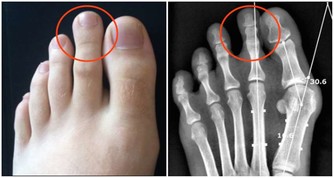

二為手足心多汗

如果手足心多汗伴有手腳心熱、口咽乾燥等,多屬於陰虛有熱;若手足心多汗伴隨腹部脹滿疼痛,大便不通,多屬於腸道內有積糞的熱證,可服用通便藥。

不同部位出汗也能判斷疾病。如頭面部出汗多為氣虛、脾胃有熱;汗液自鼻樑和鼻翼兩側滲出,多見於肺虛病人;手足多汗多因氣虛、腎虛,最好對症辨證調理。